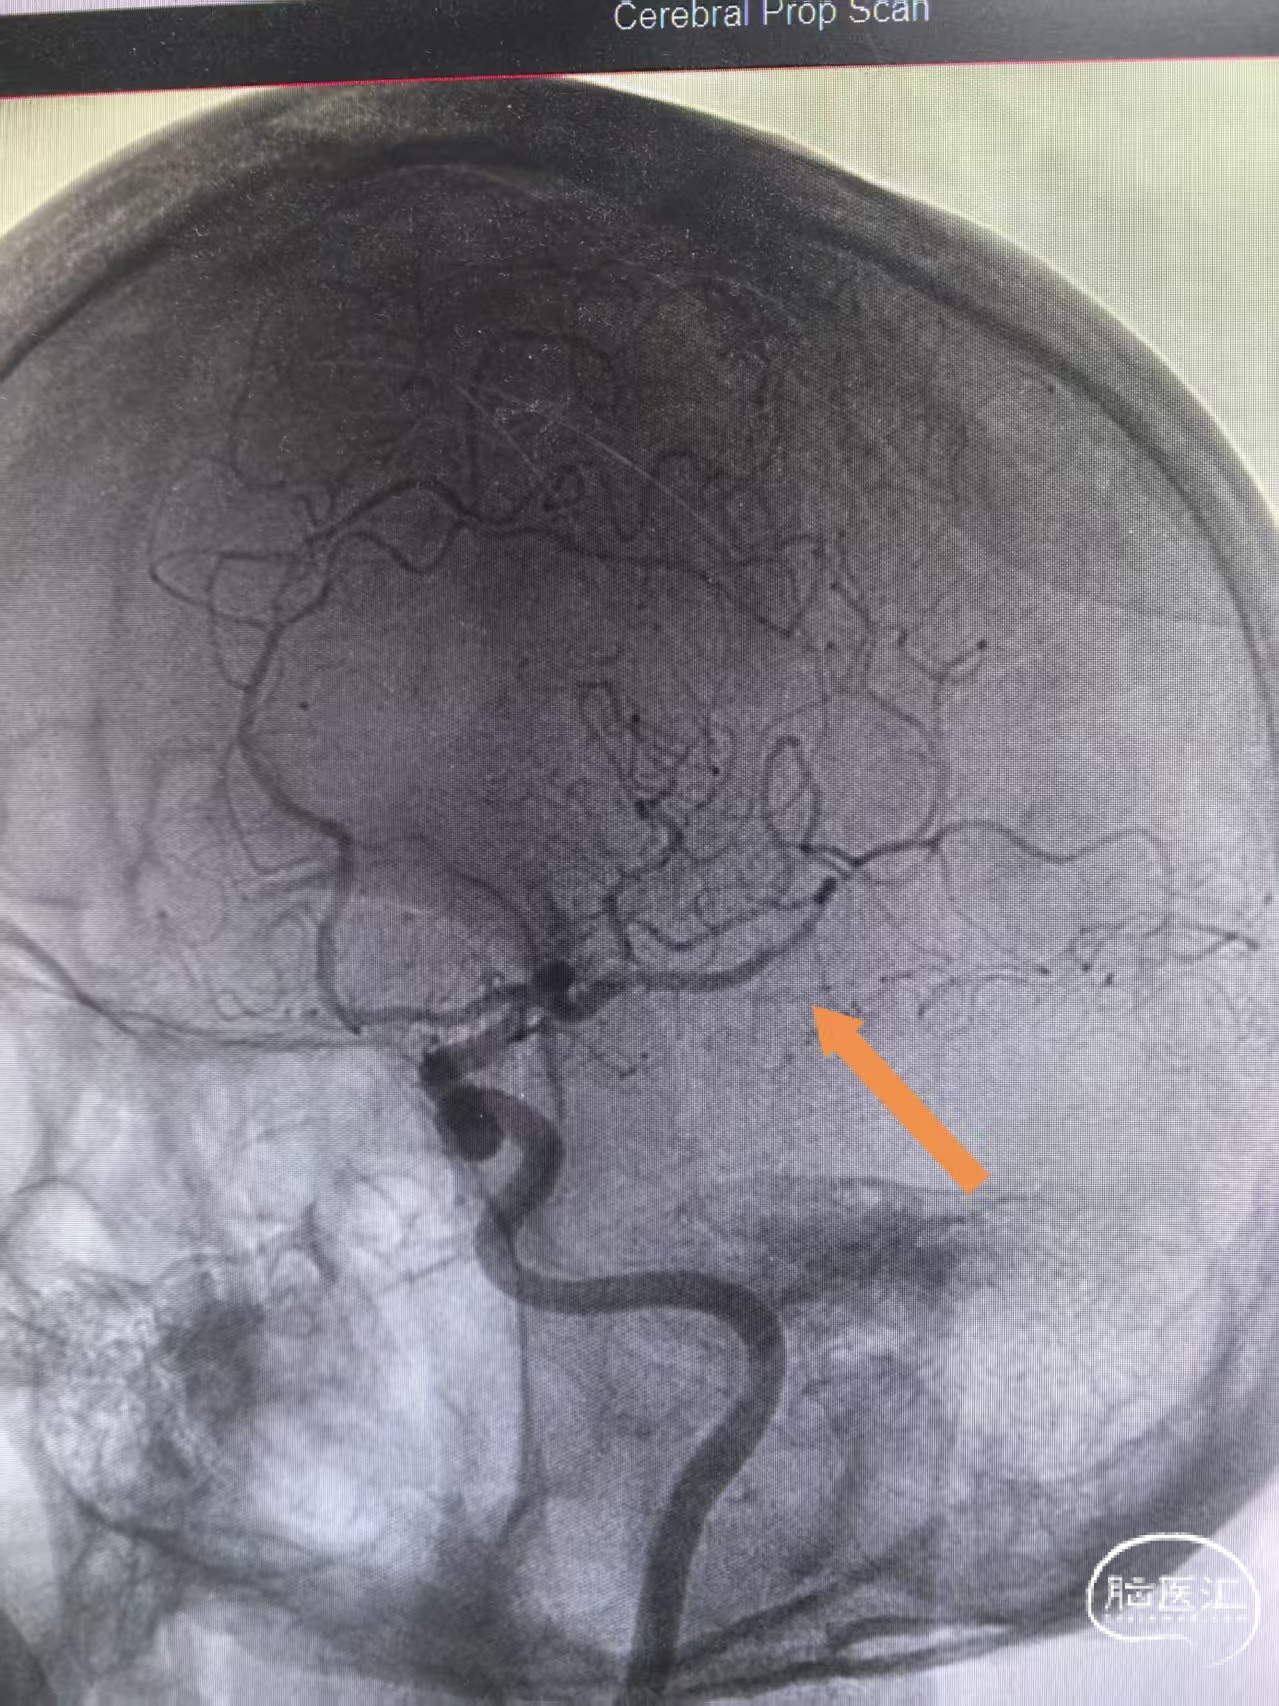

左侧颈内动脉侧位造影显示分支减少提示Mevo病变

侧位冒烟提示血管再通

颈内动脉侧位造影三级再通